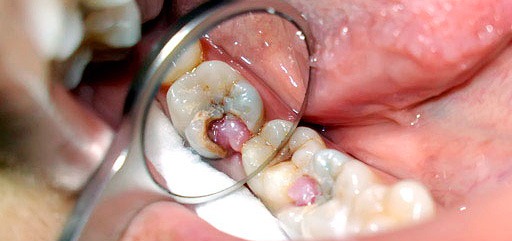

La foto mostra un "nervo" dentale estratto da una camera di polpa:

Il sondaggio consente di capire se la camera pulpare del dente è aperta, se è doloroso sondare, se il “nervo” aperto sanguina, se il dente stesso è scolorito, se c'è dolore durante la percussione (toccando il dente con l'estremità smussata della maniglia della sonda) - tutto questo ha anche importanza per la diagnosi accurata e il successivo trattamento.